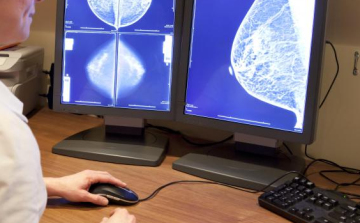

Először Magyarországon vált elérhetővé a régióban a jóindulatú emlődaganat műtét nélküli eltávolítása

A régióban elsőként Magyarországon elérhetővé vált a jóindulatú emlődaganatok egyik leggyakoribb típusának műtét nélküli eltávolítása fagyasztásos eljárással, krioablációval